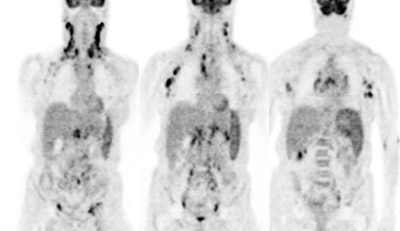

Diffuse lymphoma: In the case below, FDG PET imaging was performed prior to conventional imaging for patient staging. There is widespread tracer uptake within adenopathy in the neck, chest, abdomen, and pelvis. The spleen is enlarged and the intensity of FDG uptake is greater than the liver (SUV was 2.5) which is indicative of infiltrative splenic involvement. There was no evidence of osseous disease. (Click image to view rotating cine file) |

|